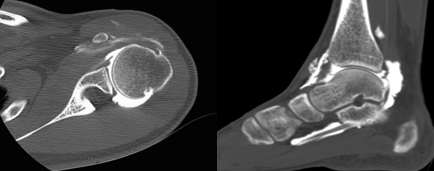

Cheville

cheville : cartilage articulaire, lésion du ligament latéral externe.